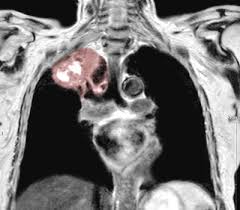

For many people with sarcoidosis, symptoms often improve without treatment within a few months or years. The decrease in other more severe symptoms is wheezing which if. Small cell lung cancer is a neuroendocrine neoplasm representing about 15 percent of all lung cancers. It causes small lumps of inflammatory cells in the lungs. The cause of sarcoidosis is unknown. By magdalena kegel | august 12, 2016. State of lung cancer report. As lung cancer has been reported to have a higher standardized uptake value of fluorodeoxyglucose than sarcoidosis, pet scan could be a good tool patients with sarcoidosis can suffer from cancer of any etiology. If your sarcoidosis goes into remission, meaning you no longer have any symptoms, your doctor may choose to slowly stop your medications. Sarcoidosis is an inflammatory disease that affects one or more organs but most commonly affects the lungs and lymph glands. Secondhand smoke causes lung cancer in adults who have never smoked. This growth can spread beyond the lung by the process of metastasis into nearby tissue or other parts of the body. The diagnosis of sarcoidosis (a chronic lung disease) and the staging of lung cancer can also be accomplished through mediastinoscopy.

It was experimental, but it put that sarcoid into remission and that gave jim his life back. Given the diagnostic dilemma, we. The diagnosis of sarcoidosis (a chronic lung disease) and the staging of lung cancer can also be accomplished through mediastinoscopy. The disease is referred to as systemic lesions. Helen has now had treatment for her lung cancer and is recovering well.

Case 25 2020 A 47 Year Old Woman With A Lung Mass Nejm from www.nejm.org A case of primary lung cancer associated with sarcoidosis. Because sarcoidosis can escape diagnosis or be mistaken for several other diseases, we can only guess at how many people are affected. Sarcoidosis is currently thought to be associated with an abnormal immune response. The decrease in other more severe symptoms is wheezing which if. Medically reviewed by jay zatzkin, md; This growth can spread beyond the lung by the process of metastasis into nearby tissue or other parts of the body. Treated her nodal involvement as small cell lung cancer. By magdalena kegel | august 12, 2016.